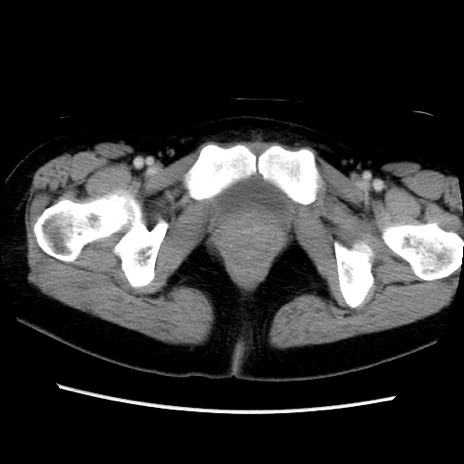

症例39(横断像)

【症例】40歳代女性

【主訴】上下腹部痛

【現病歴】2日目から下腹部痛あり。夜間は痛みで眠れなかった。昨日より上腹部痛と下痢が出現。臥位で痛みは軽快したため、休んでいた。本日になって臥位でも立位でも痛みが強くなってきたため救急要請。

【既往歴】子宮内膜症

【身体所見】部:平坦・軟、左上下腹部に圧痛あり、反跳痛あり。

【データ】WBC 21800、CRP 26.78